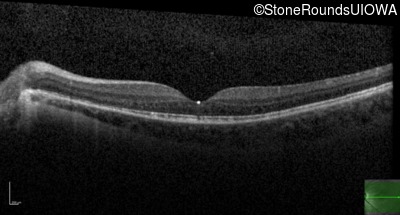

Optical Coherence Tomography - Right - 20/40 +1

Exemplar / OCT Stack